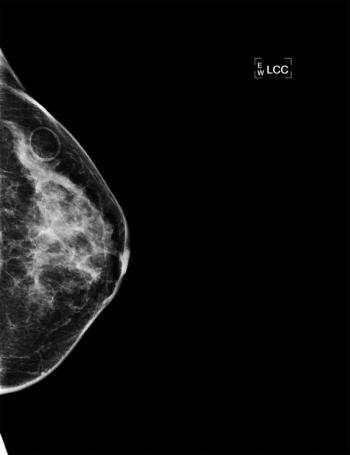

Image IQ: 52-year-old Female with Family History of Breast Cancer

ByCarla de Venecia, MD,Erini Makariou, MD

52-year-old asymptomatic female with family history of breast cancer presents for annual mammogram.